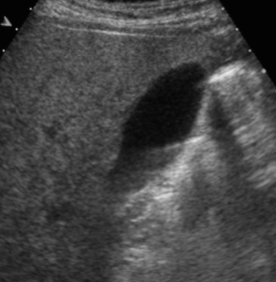

Enhancement

Caused by a structure of low attenuation adjacent to a structure of normal attenuation

Appears as a band of increased echogenicity behind an area of low attenuation

Reduced by:

Gain & TGCs

Spatial compounding

Can be diagnostically useful to distinguish fluid-filled from solid objects

Fluid filled objects have this artifact

Solid objects DO NOT have this artifact